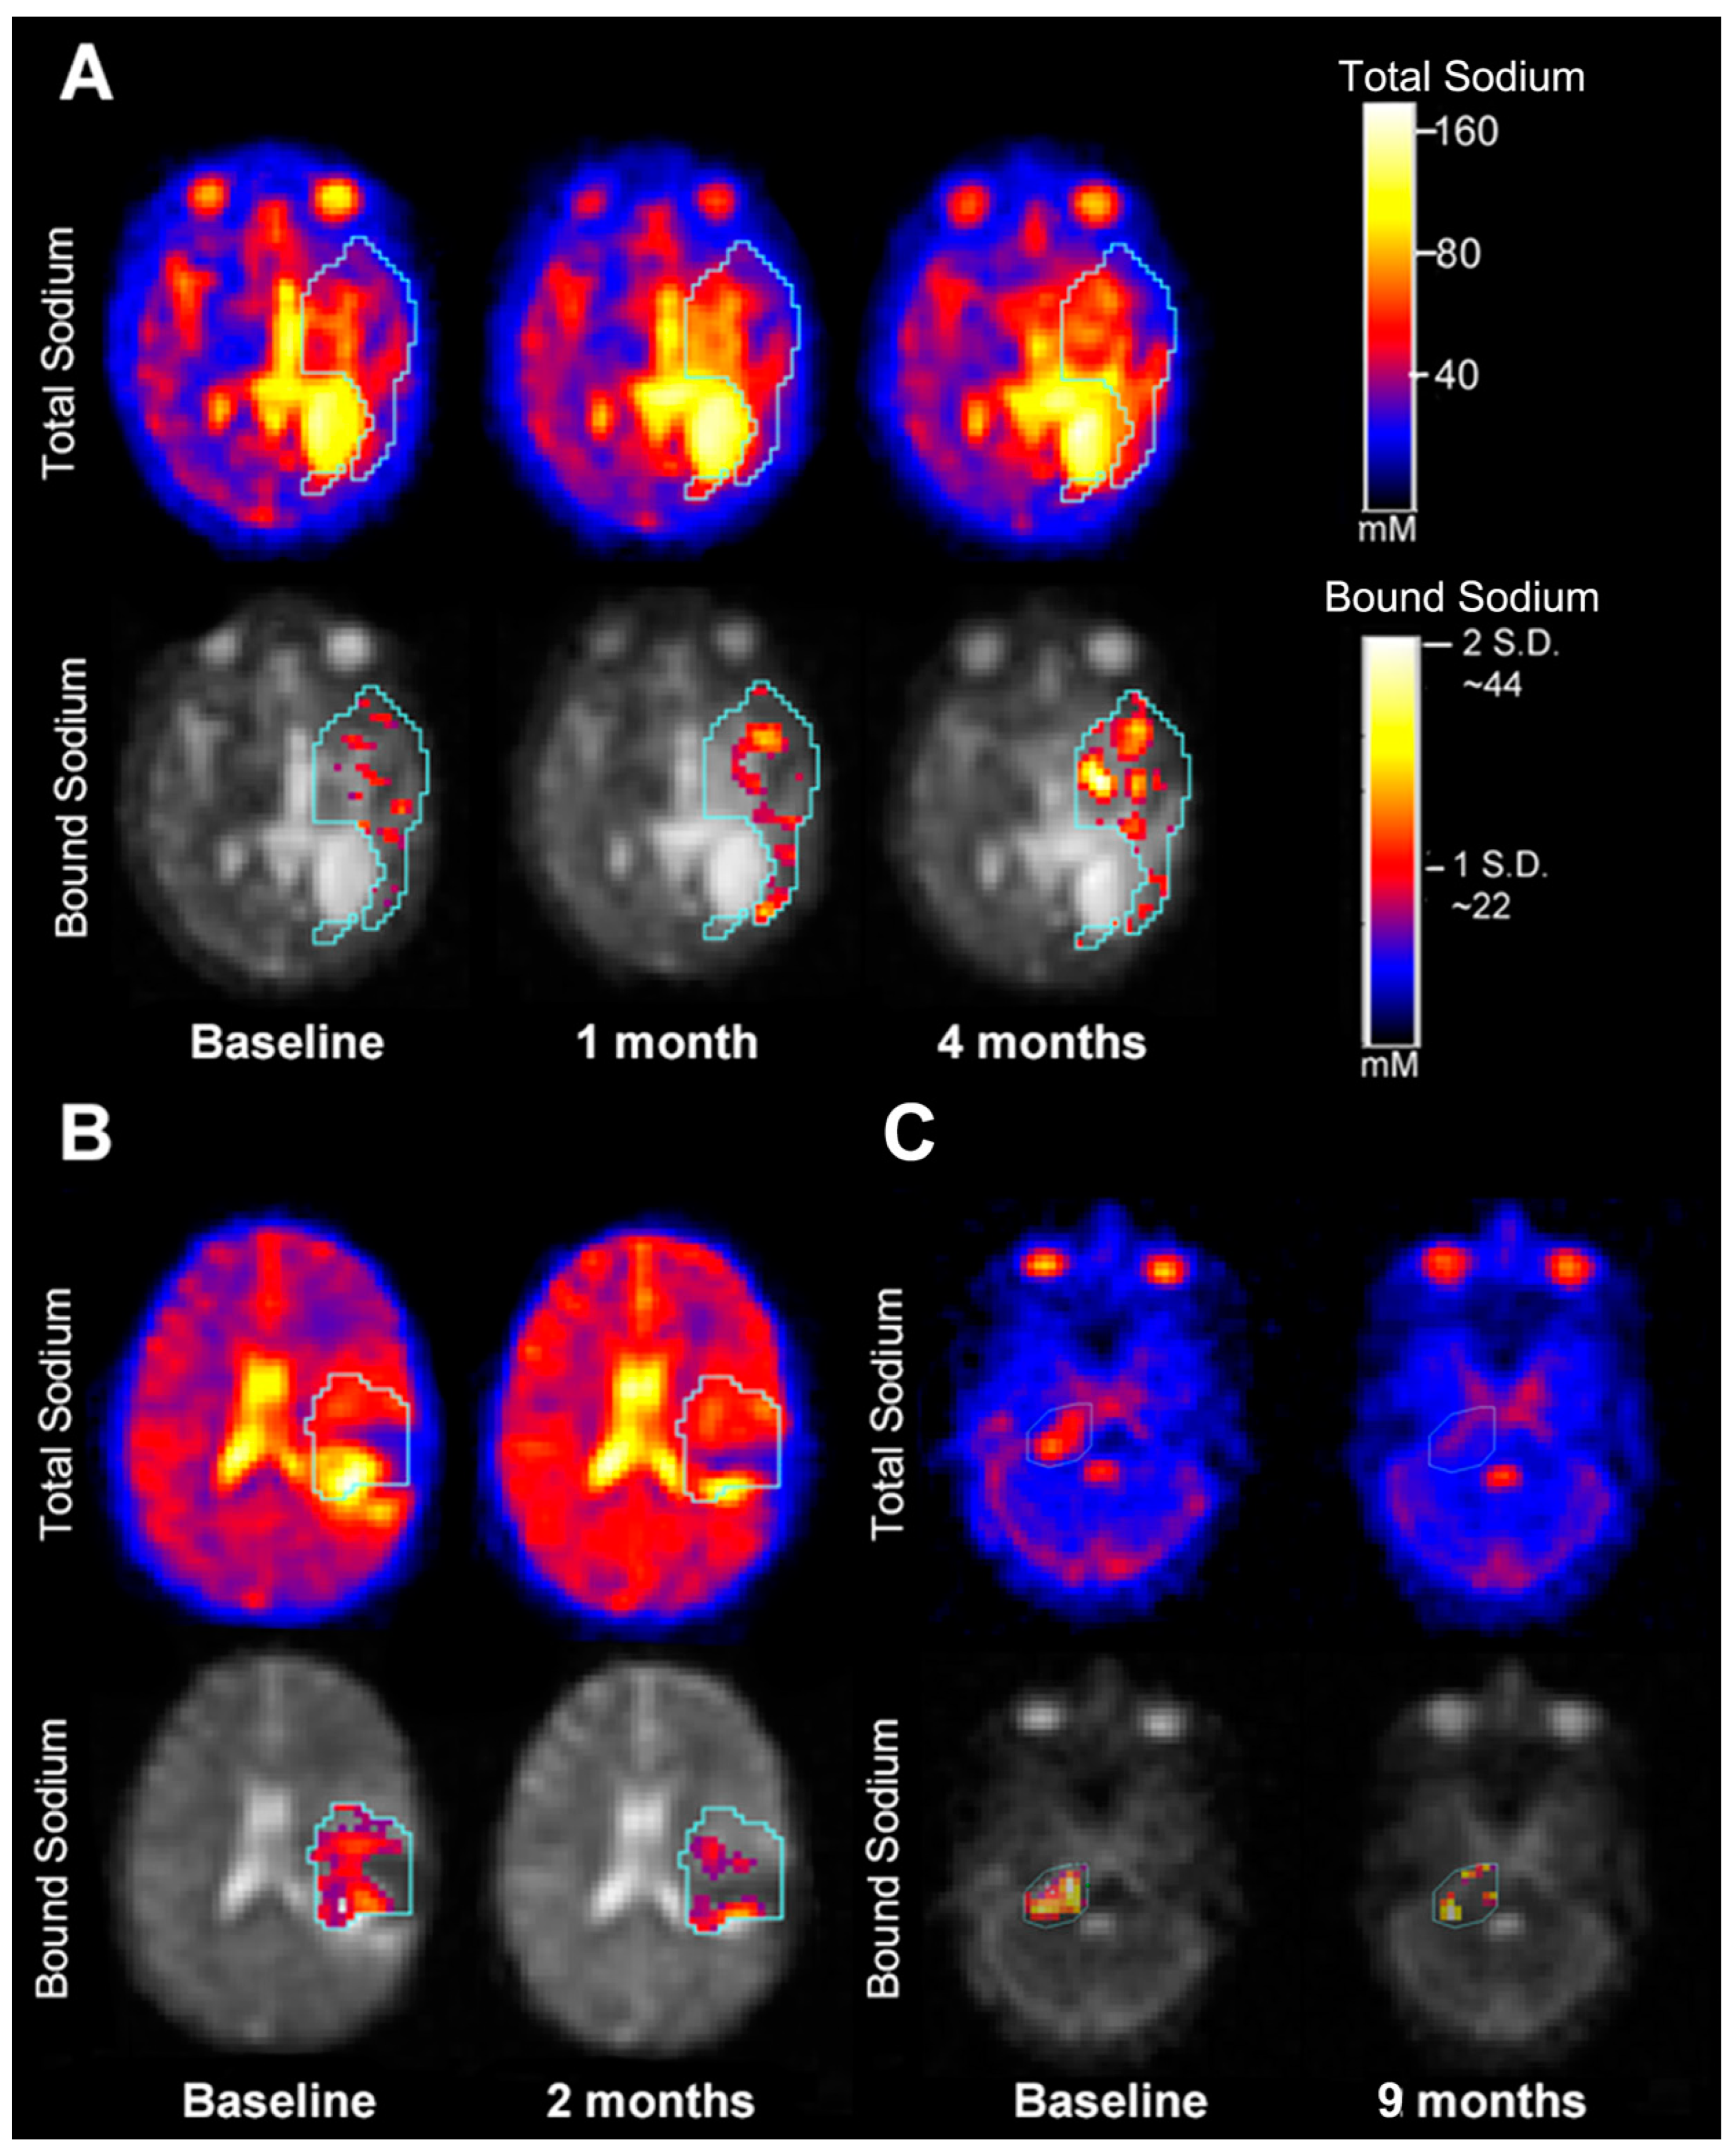

3.4. Quantitative Intra-Tumoral Bound Sodium Concentration of Pediatric Gliomas Including Serial Imaging

| 4010-1 | HGG | 92.5898 | 12.3779 | First serial scan showed decrease in size of the tumor. The second serial scan showed a decrease in size of the tumor The third serial scan showed necrosis with increase in size of the tumor as well as new enhancing lesion The fourth serial scan showed no change in size of the tumor | 163.6 | |||||

| 4010-2 | 73.9051 | 15.4974 | −18.6847 | −20 | Decrease | 120.7 | −42.9/−36% | Concordant | ||

| 4010-3 | 60.0018 | 14.2077 | −13.9033 | −19 | Decrease | 45.3 | −75.4/−166% | Concordant | ||

| 4010-4 | 67.2067 | 20.0919 | 7.2049 | 12 | No change | 43.5 | −1.8/−4.1% | Discordant | ||

| 4010-5 | 62.0964 | 13.6286 | −5.1103 | −8 | No change in TSC; decrease in BSC including recurrent lesion between last two dual echo scans | 33.8 | −9.7/−28.7% | Concordant | ||

| 4023-1 | HGG | 49.477 | 3.7975 | 7.7313 | 16 | Increase | Interval increase in non-enhancing edema. Infiltrating abnormal signal intensity representing tumor progression | 19.2 | ||

| 4023-2 | 57.2083 | 4.3588 | 39.4 | 20.2/51.3% | Concordant | |||||

| 4025-1 | HGG | 47.0821 | 8.8937 | −11.7503 | −25 | Decrease in TSC and decrease in BSC | Interval increase in size and enhancement of tumor representing recurrence | 26.8 | ||

| 4025-2 | 35.3318 | 5.7061 | 20.4 | −6.4/−31.4% | Concordant | |||||

| 4027-1 | HGG | 77.1108 | 13.6791 | No change in TSC on both serial scans; increase in BSC in recurrent lesion between last two dual echo scans | Progressive increase in size of tumor representing tumor progression | 1 | ||||

| 4027-2 | 81.9984 | 17.2532 | 4.8876 | 6 | 12.9 | 11.9/92.2% | Discordant | |||

| 4027-3 | 78.9372 | 18.4989 | −3.0612 | −4 | 48.6 | 35.7/73.5% | Discordant | |||